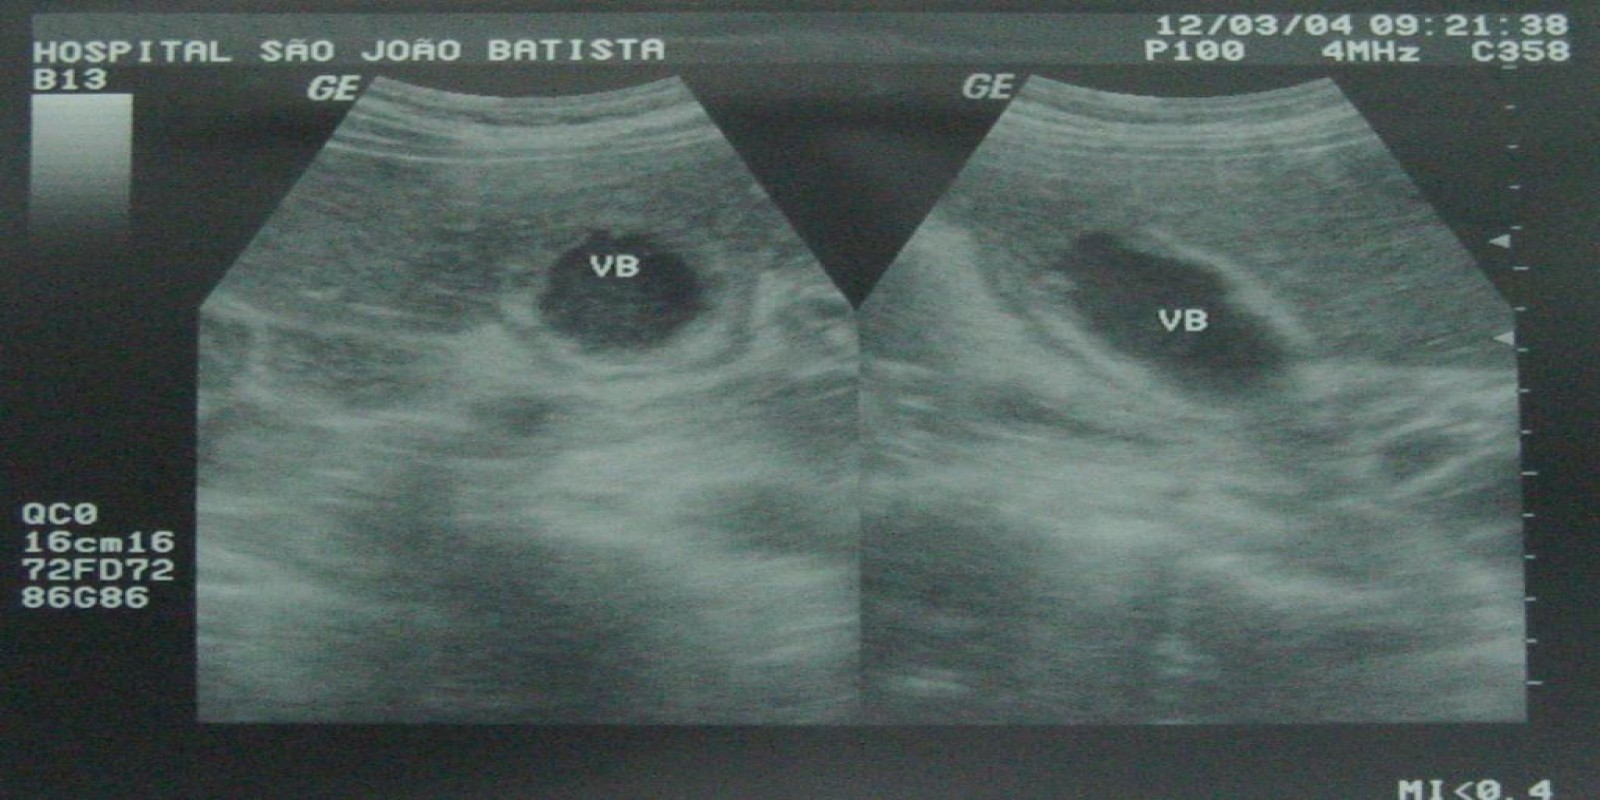

Caso Código 054G de Colecistite Aguda

Cod.: 054G